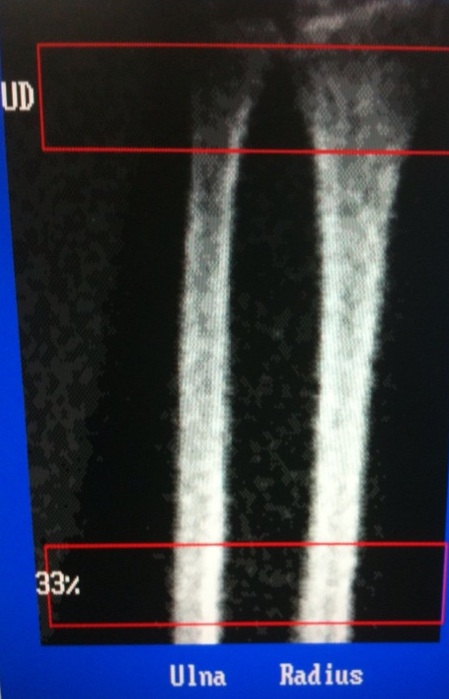

Διαγνωστική εικόνα

Στο αποτέλεσμα που εξάγεται αυτόματα από τα μηχανήματα μέτρησης οστικής πυκνότητος διακρίνουμε ακριβώς ότι αναφέρεται στα γενικά. Aπεικονίζεται η οστική πυκνότητα της κερκίδας και της ωλένης στην περιοχή της κερκιδοωλενικής εντομής - UD (σπογγώδες οστούν) και στο 1/3 του αντιβραχίου-33% (φλοιώδες οστούν).